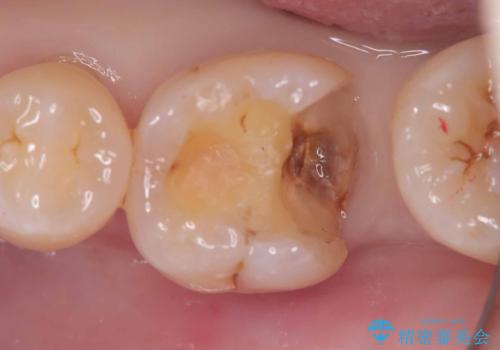

- 銀歯の下に虫歯が見つかりました。一度治療されている歯であり、レントゲン上では虫歯が神経に近い位置まで進行している様子が確認されました。

ただし、自発痛の既往はなく、歯髄診の結果も正常であったため、虫歯除去中に露髄した場合には生活歯髄療法(VPT)を行う方針としました。